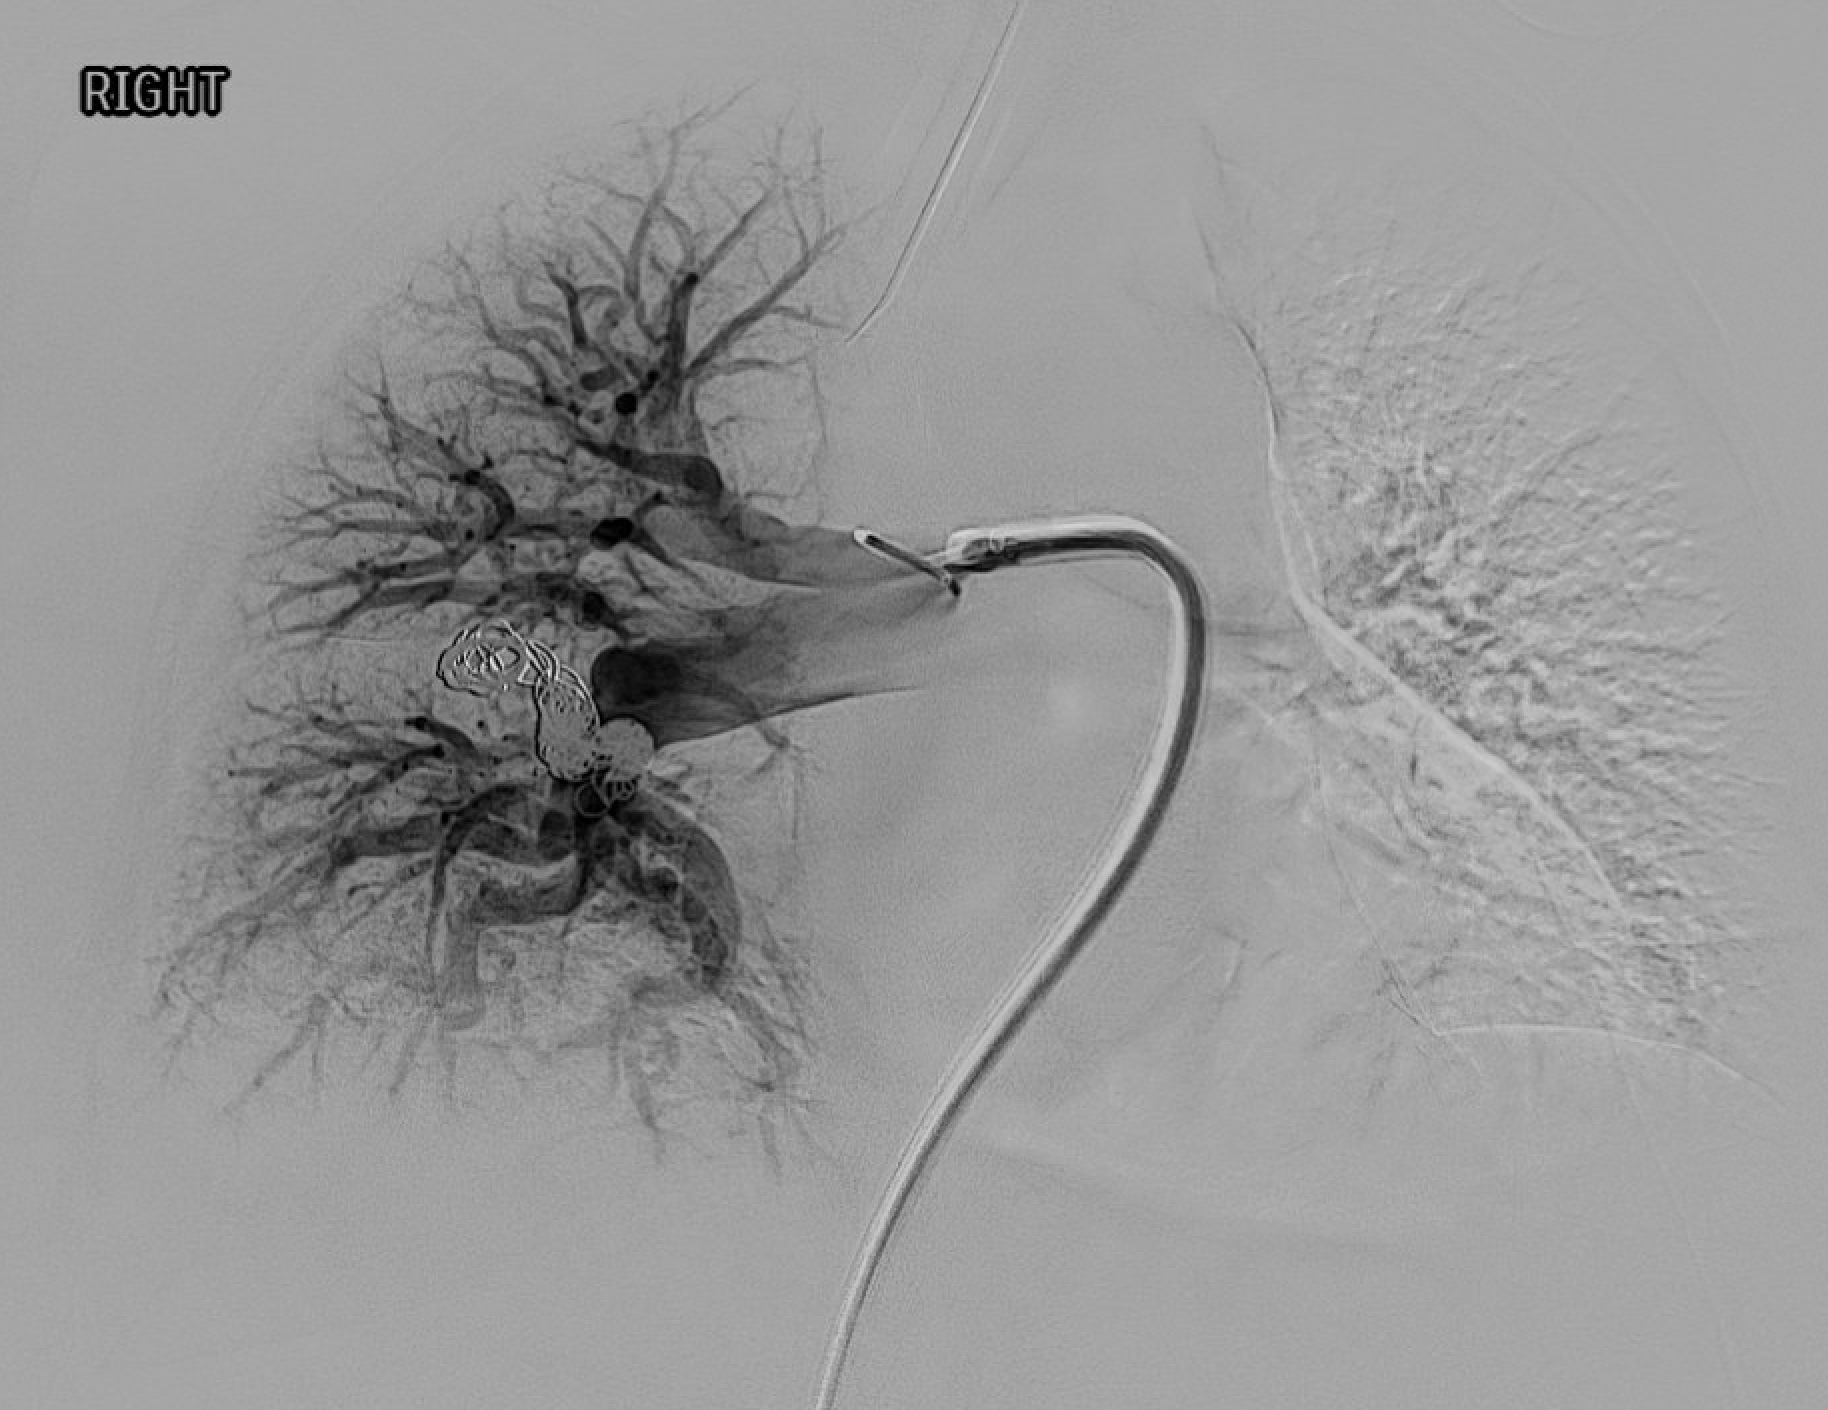

Pre-embolization pulmonary angiogram — contrast filling of the AVM sac via the feeding segmental artery.Post-embolization — coils in the feeding artery with stasis and no residual sac filling on completion angiogram.

Completion angiogram: confirm cessation of flow into sac and persistent perfusion of normal segmental branches. Address any additional feeders before case end.